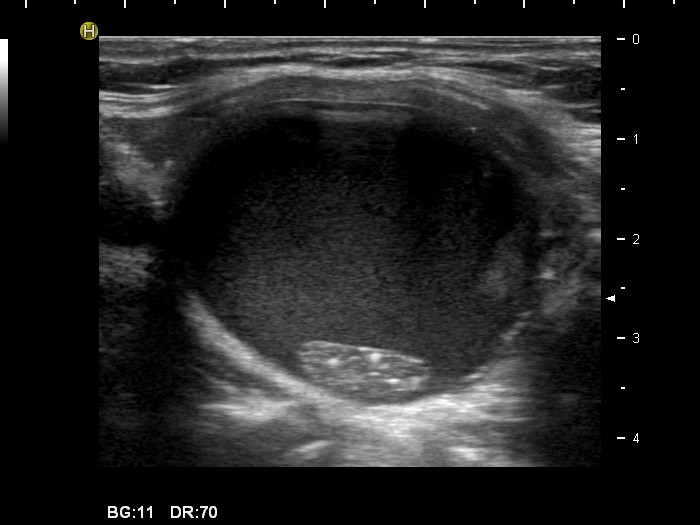

Follicular adenoma - Case 8. (ultrasonographic picture 7)

Left lobe, longitudinal scan.